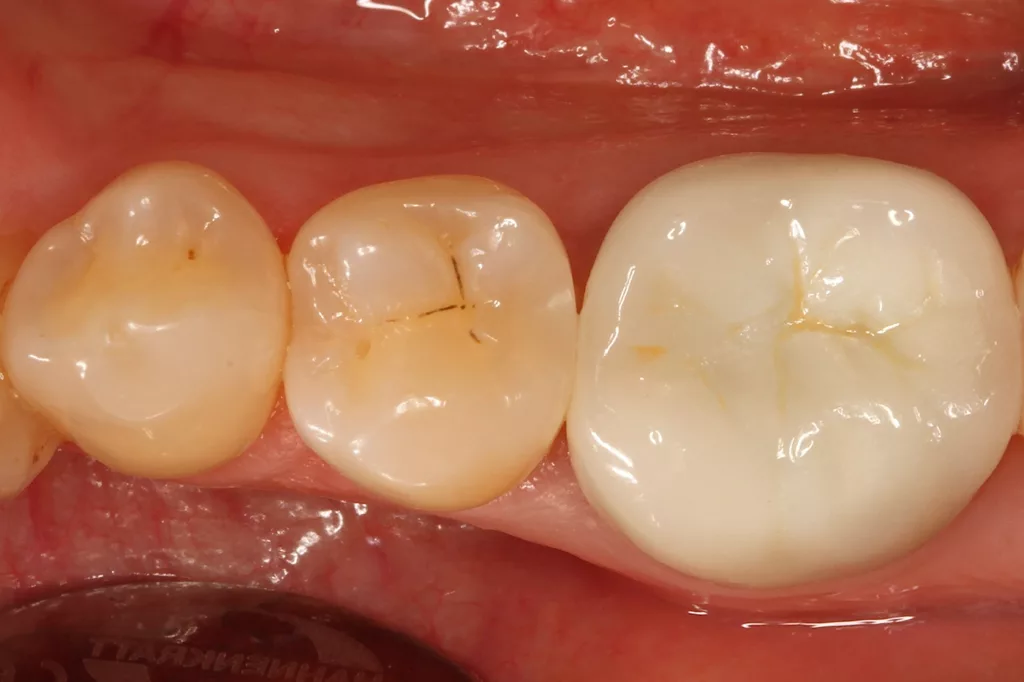

Fall 1: Versorgung einer Initialkaries an Zahn 45

Bei der 54 Jahre alten Patientin fiel eine versteckte Approximalkaries distal an Zahn 45 auf (Abb. 1). Nach Eröffnung des Defektes (Abb. 2) zeigte sich das Ausmaß des stark unterminierenden Defektes. Nach vollständiger Kariesexkavation, Präparation des Defektes und Ausformung der Kavität mit einer Teilmatrize (Danville ultra thin flex, Zest Dental Solutions, CA, USA), einem Kunststoffkeilchen (G-Wedge, Garrison, MN, USA) und einem NiTin-Prämolaren-Spannring (re-invent Dental Products GmbH, Abb. 3) erfolgte erneut unter relativer Trockenlegung nach adhäsiver Vorbehandlung (G2 Universal, GC, total etch) die Versorgung mit dem niedrigviskösen Visalys Bulk Flow – diesmal in einem einzigen Inkrement (Abb. 4). Das Material ließ sich nach der Applikation mit einer Sonde ausformen und die Randleiste durch Verstreichen an der Innenseite der Matrizenfolie so gut darstellen, dass nach Abnahme der Matrize kaum noch Ausarbeitungsaufwand bestand.

Die Polymerisation erfolgte zunächst für 20 Sek. aus okklusaler Richtung (Elipar Deep Cure, 3M), nach Abnahme der Matrize erfolgten zwei weitere Härtungszyklen für nochmals 20 Sek.: einmal aus bukkaler Richtung sowie ein Nachhärten der Restauration mit mittig okklusal auf dem Zentrum der Füllung platziertem Lichtaustrittsfenster. Die Abbildung 5 zeigt die Restauration unmittelbar nach Ausarbeitung und Politur (Diacomp Plus Twist, EVE). Die sehr gute Farbanpassung beeindruckt: Das Material erscheint auf keinen Fall zu transluzent, obwohl es in einer 4-mm-Bulkanwendung eingesetzt worden war. Durch die Versorgung des kleinen Defektes in einem einzigen Inkrement reduziert sich neben der Arbeitszeit auch das Risiko einer nicht bemerkten Defektstelle zwischen Einzelinkrementen bei derart schwer einseh- und kontrollierbaren Kavitäten. Das Ergebnis spricht unter ästhetischen und funktionellen Aspekten für sich. Die Abbildung 6 zeigt die klinische Situation bei einer Nachkontrolle nach sechs Monaten: Es sind weder Randverfärbungen noch Desintegration erkennbar, die Ästhetik ist unverändert.